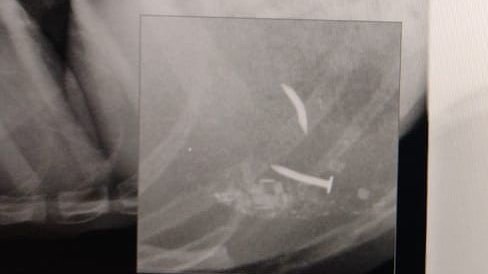

Cabe mencionar dos situaciones días antes habían sacado a unos animales entre ellos un pitbull con clavos en el intestino ya que los hacia comer clavos le arrancó los dientes tenia clavos a un costado del tórax el animal tuvo que ser sacrificado debido a las lesiones. En la mañana antes de la detención del presunto torturador retiro del domicilio otros animales torturados los cuales no se han encontrado. Sus torturas incluían criar gatos perros patearlos quemarlos clavarlos robar mascotas perros gatos y otros clavarlos en los huesos etc, los vecinos se dieron cuenta por los alaridos de los animales torturados, es un peligro para la sociedad cuenta con familiares en la política hecho por el cual ha podido salir sin complicaciones de las anteriores denuncias pero no vamos a permitir más abuso animal recordemos que los asesinos seriales empiezan con estos actos psicopatas apoyen la firma por favor